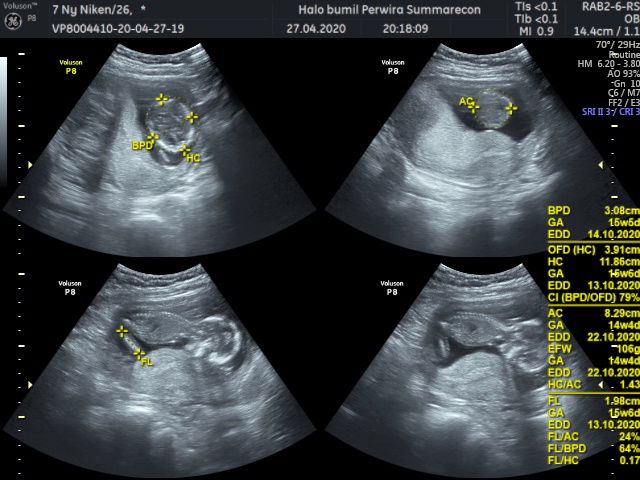

Usg 4d debayku

Assalamu’alaikum bunda Ini hasil 4d aku, yg kemarin terupload yg 2d sekarang 4d nya ? Alhamdulillah dedenya sehat dan aktif banget usianya minggu ini 15 weeks ?? oh iya dedenya pas di usg sedang menghadap ke punggungnya bunda loh dia malu sm dokter ?